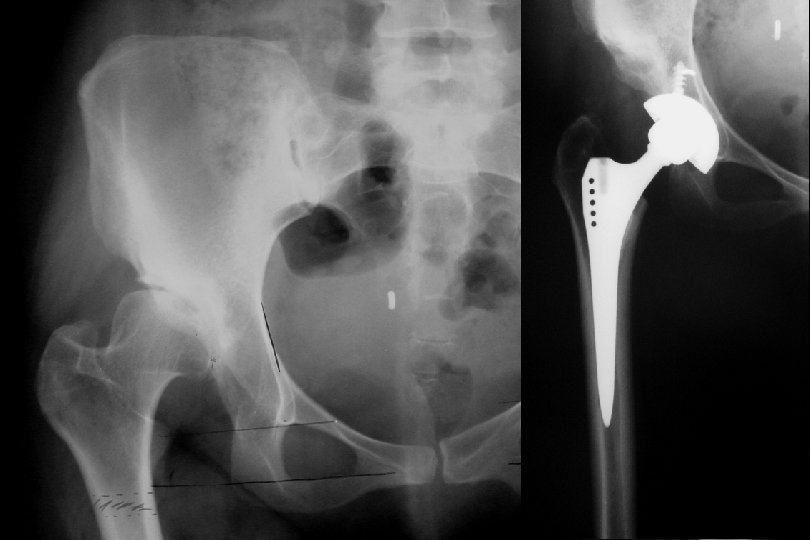

Genç adult Reluksasyon Hareket kısıtlılığı Avasküler nekroz Displazi, sublukse kalçalarda Ase-femur baş uyumunu artıran Girişimler Tamamen çıkıklara dokunulmamalı !!!

Sekonder dejeneratif osteoartrit TEMAS ALANI = 26. 7 cm Birim alana düşen yük miktarı = 23 kg/cm 2 TERS ORANTI

Adult • Artrodez !!! • Total Eklem Replasmanı • Genç ve aktif yaştalar • İyileştirilmiş malzemeler kullanılmalı • Hasta çok detaylı bilgilendirilmeli